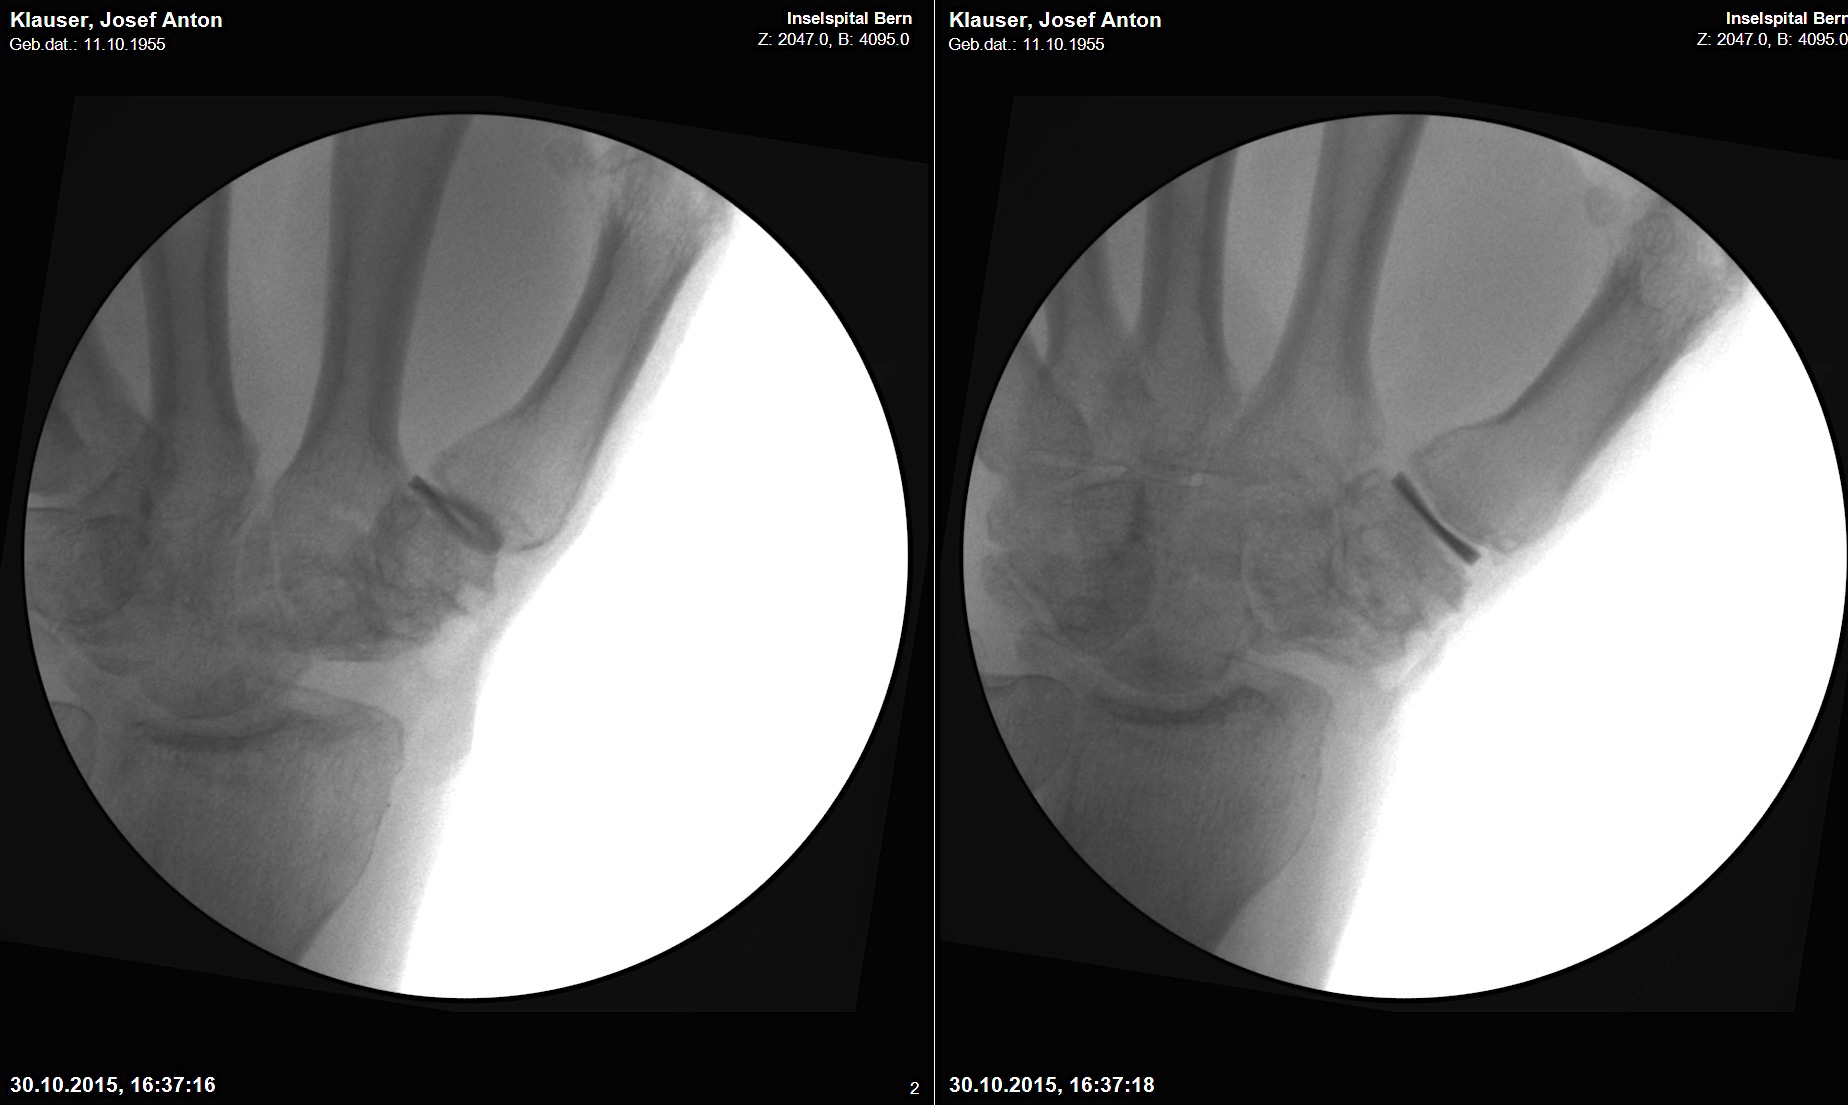

A 20-year-old male suffered a complex multi-digit injury of the right hand requiring revascularization and stabilization of both proximal phalanx and PIP joint fractures (Figs 5 - 8). Multiple plates, including the rotation correction plate from the 1.5 module of the VA Locking Hand System were used for fixation. The Variable Angle Locking system is ideal when only two screws, either proximal or distal, are able to be inserted due to space limitation.

One major advantage of variable angle technology in very distal phalangeal fractures is the ability to be extremely flexible with a wide range of fixation options. Freedom of implant placement assists early mobilization, vital in these complex fractures with associated soft-tissue trauma.